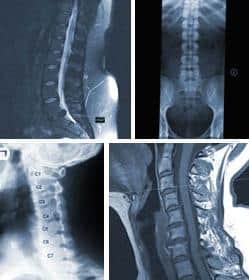

Imaging Tests

Common tests for a patient with low back and lower extremity pain may undergo include lumbar spine x-rays (films), CT scans (computed axial tomography scans), MRI scans (magnetic resonance imaging), myelograms, post myelographic CT scans, EMG/NCV (electromyogram/nerve conduction velocity) studies, discograms, and bone density tests.

• Lumbar spine films: these plain x-rays are good at showing alignment of the spine. Degenerative changes, thinning disc space, any slippage, known as spondylolisthesis or subluxations, are easily visible on plain x-rays. Also, compression fractures of the vertebral bodies are easily seen. Tumors can also be detected with plain film radiography.

• CT scans: these show "cross sections" of the spine. They are pictures of the body divided into very small slices. These "slices" of the body, can accurately reveal the anatomy within. When used on the spine, they detail bone very well, but are not quite as good at showing soft tissues, such as herniated discs, nerves and tumors. CT scans use x-rays, which are sent through the area of interest in numerous directions, then a computer adds the images in 3-dimensions, and then displays the pictures so they can be easily understood by your doctor.

• MRI scans: the images provided are similar to CT scans; in as far as these images provide serial slices through the spine, or other areas of interest. They use magnetism, instead of x-rays, to get the images. Besides showing information in additional planes, the MRI gives much better detail of the soft tissue anatomy of the spine, than does CT scans. Discs, nerve roots, and tumors are all seen more clearly. On the other hand, bone is seen better on CT scans.